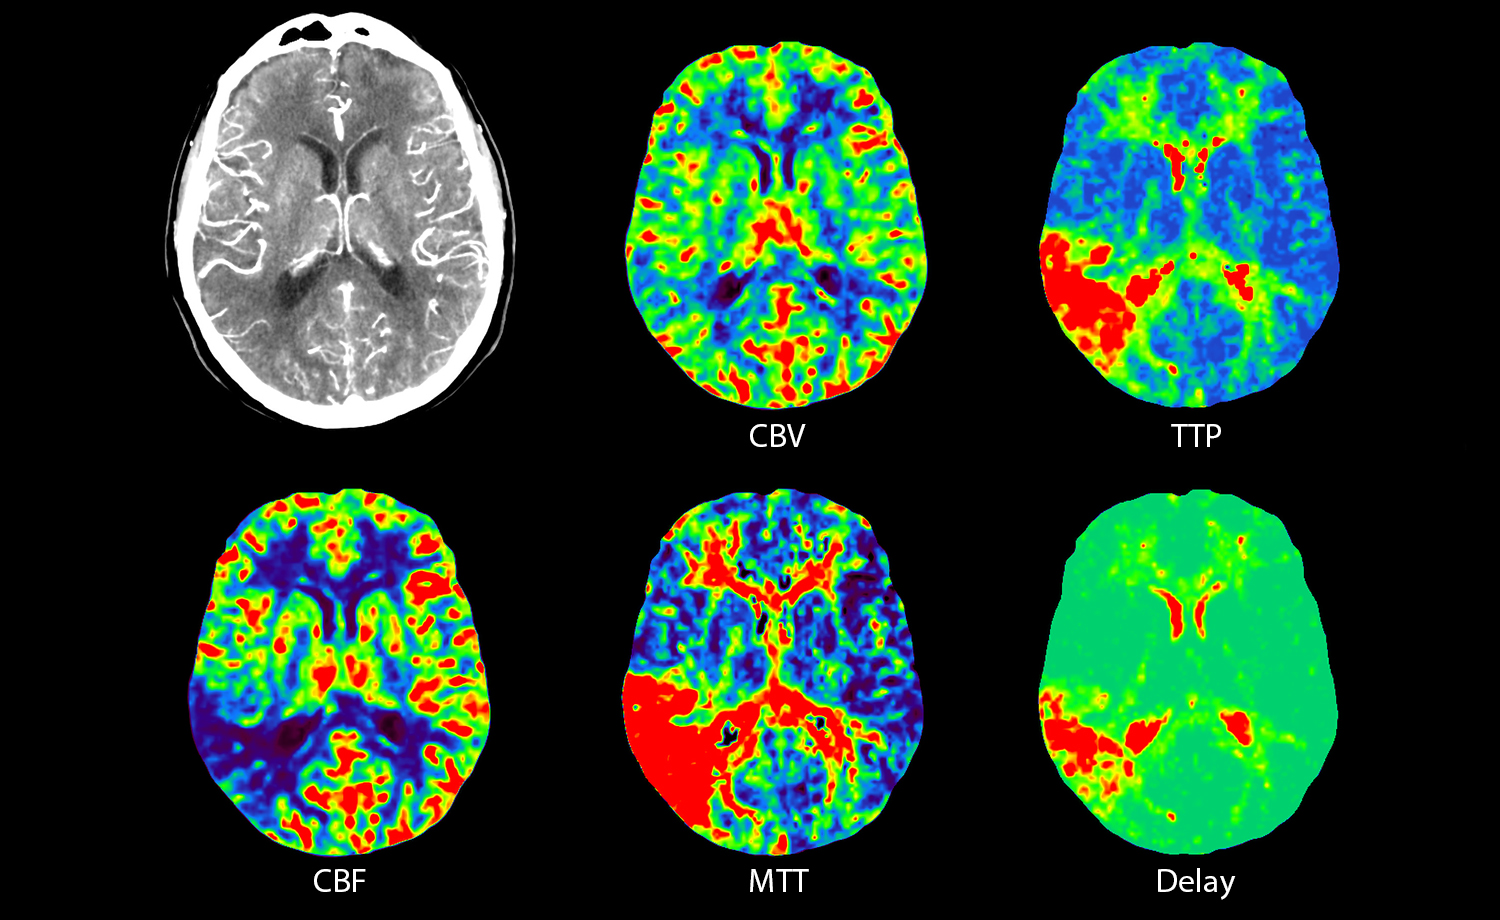

Neuro CT

When it comes to brain, every second counts

Stroke evaluation platform performs whole brain perfusion imaging and 4D digital subtraction angiography of the intracranial circulation in just one minute. Plus, with advanced 4D brain perfusion software, you can evaluate flow and perfusion defects in under five minutes.